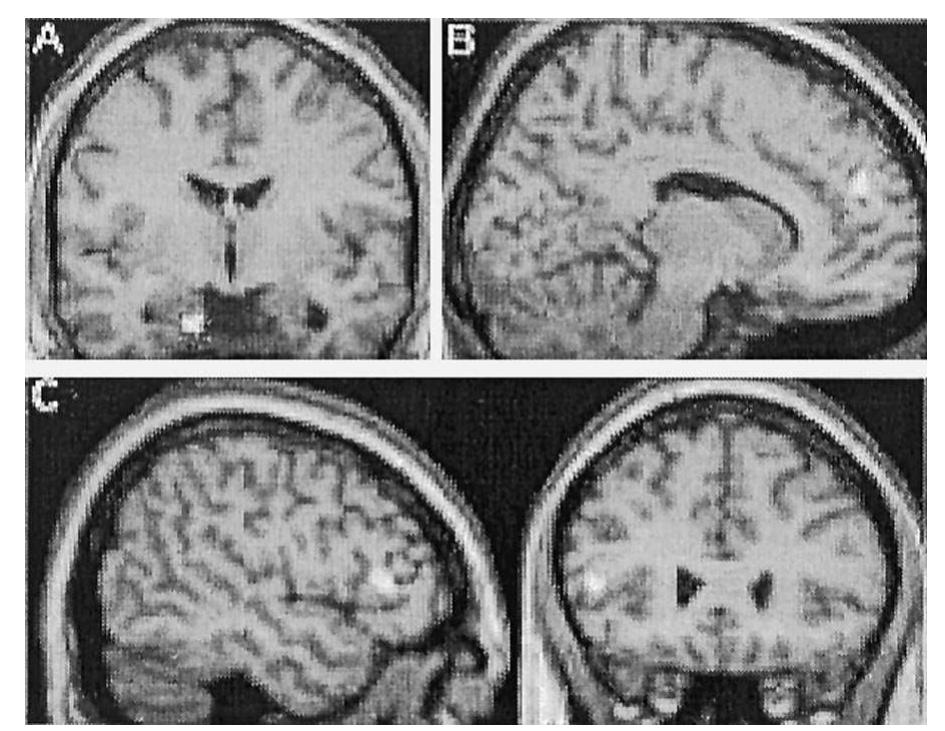

AUTISM is a biological disorder which affects social cognition, and understanding brain abnormali... more AUTISM is a biological disorder which affects social cognition, and understanding brain abnormalities of the former will elucidate the brain basis of the latter. We report structural MRI data on 15 high-functioning individuals with autistic disorder. A voxel-based whole brain analysis identi®ed grey matter differences in an amygdala centered system relative to 15 age-and IQmatched controls. Decreases of grey matter were found in anterior parts of this system (right paracingulate sulcus, left inferior frontal gyrus). Increases were found in posterior parts (amygdala/peri-amygdaloid cortex, middle temporal gyrus, inferior temporal gyrus), and in regions of the cerebellum. These structures are implicated in social cognition by animal, imaging and histopathological studies. This study therefore provides converging evidence of the physiological basis of social cognition.